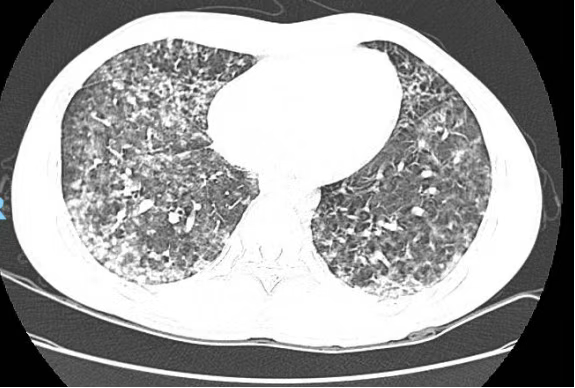

文先生意识到情况不妙,急忙前往广州医科大学附属番禺中心医院急诊就诊。经过紧急检查,医生发现他的氧合指数差,感染相关指标显著升高,同时出现了肝、肾功能损伤、血小板下降和凝血功能异常等多脏器功能损害。胸部CT显示双肺多发感染性病变,病情危急,他被立即收入重症医学科进行治疗。

患者胸部CT显示双肺多发感染性病变